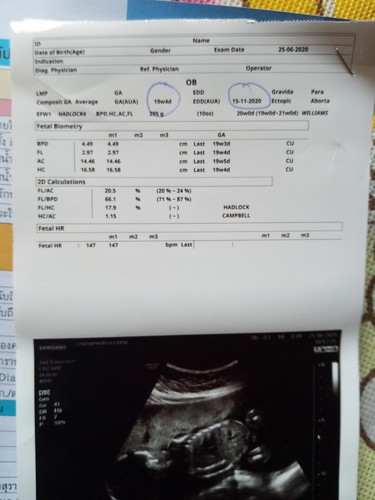

ในนี้ไม่มีบอกค่ะ ส่วนมากหมอจะแจ้งเอง หรือมีบอกในรูปซาวด์ค่ะ

ในใบซาวใม่มีบอกเพศค่ะ บ้านนี้หมอบอกเองค่ะว่าน้องเพศใหน

ไม่เห็นเขาเขียนบอกเลยค่ะ Gender

Gender คือเพศค่ะ